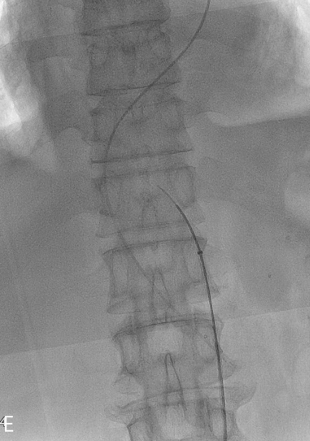

Fig 2E

(E) Fenestration from true lumen to false lumen was performed using transseptal needle under the ultrasound guidance.

(F, G) Abdominal ultrasound transverse and longitudinal view demonstrated the aortic dissection and guide the fenestration.

Fig 2G